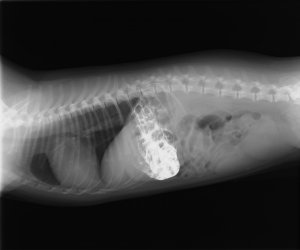

レントゲン検査をしてみると、胃内に何か物が認められます。これが吐気の原因のようです。

こちらは、造影剤投与後のレントゲン写真です(この時点では、胃内異物が何であるか判明しませんでした。)

この後、時間をあけて再度撮影しましたが、胃の内容物は全く移動しませんでした。胃停滞が生じているようです。

それにともない、腸内のガス貯留像が増えてきました。あまり良い所見ではありません。